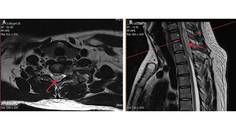

Case Report: Longitudinally Extensive Transverse Myelitis

Ylec Mariana Cardenas, MD; Lakshmi Leishangthem, MDYlec Mariana Cardenas, MD; Lakshmi Leishangthem, MD - Imaging & Testing